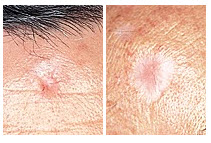

Basal Cell Carcinoma (BCC) Photos

A small pink growth with a slightly raised, rolled edge and a crusted indentation in the center. (BCC)

Basal Cell Carcinoma (BCC) Case Study

Inconvenient BCC, Good Outcome

Deborah S. Sarnoff, MD

A patient in his 40s with the genetic condition known as Gorlin syndrome had been treated for many basal cell carcinomas. During the COVID pandemic, he noticed a new bump on his upper lip. It didn’t seem serious to him, so, like many patients during that time, he did not see his dermatologist. When he finally did get checked, it was indeed a BCC and had grown deep enough to require several stages of Mohs surgery. The surgery eliminated the cancer but left the lower part of his face disfigured (top photo). Dr. Sarnoff’s business partner and husband, plastic surgeon Robert H. Gotkin, MD, was able to reconstruct the area with minimal scarring and an excellent cosmetic result (bottom photo, after healing). Read the full story here: https://skincancer.org/blog/we-dont-want-to-scare-you-but/